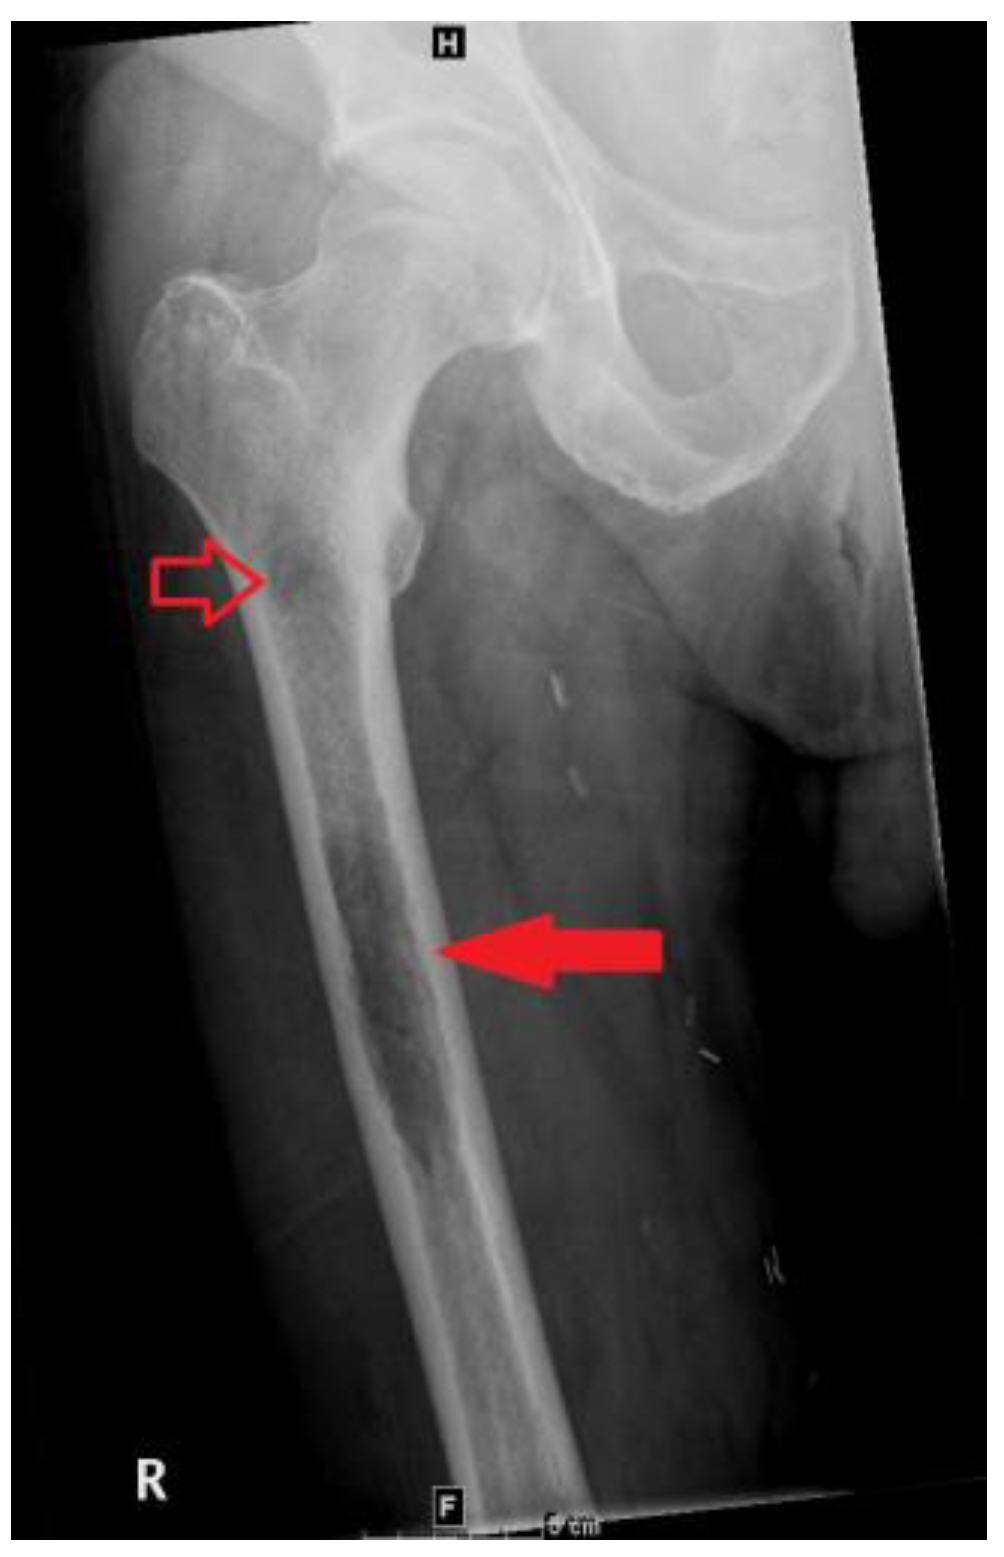

A bone scan showed a right maxillary sinus mass extending into the orbital floor, as well as increased activity from the proximal right femur to the mid shaft, and the left sacrum. A cardiac MRI revealed an irregularly shaped mass invading the superior vena cava and up to the atrial free wall (Figure 1). The X-ray of the right femur showed a large lytic lesion and multiple small lesions in the proximal right and left femur (Figure 2). Magnetic resonance imaging (MRI) of the brain and cervical spine further confirmed the right maxillary sinus mass extending through the orbital floor and into the pterygopalatine fossa and inferior orbital fissure (Figure 3).

Figure 2.

Frontal view radiograph of the right femur demonstrating a 10 cm in length lytic lesion of the proximal half of the femoral diaphysis (solid arrow), with a smaller lesion more proximally (open arrow).